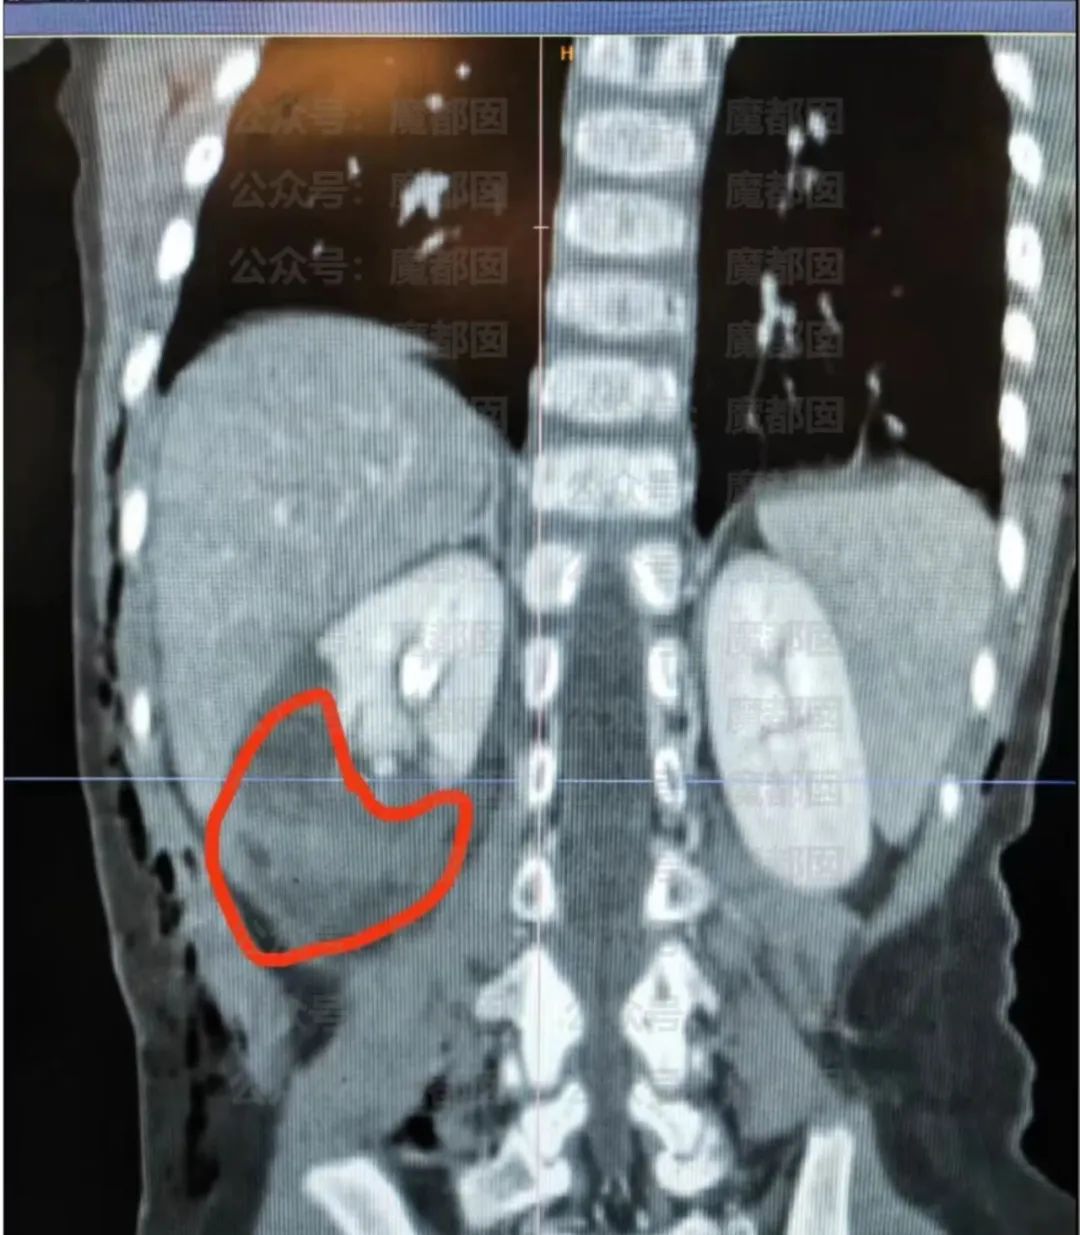

鄧女士傷勢較輕,2歲半的糖糖受傷非常嚴(yán)重:

全身多處犬咬傷,胸背部多處皮膚裂傷,胸腔內(nèi)有積液,右側(cè)肋骨骨折,最嚴(yán)重的是右腎破裂伴血腫形成。

正常情況下,我們的腎臟會(huì)被一團(tuán)脂肪包裹著,只有狗咬的沖擊力撕開皮膚,又撕破脂肪緩沖,才會(huì)導(dǎo)致腎臟破裂。

可見,狗咬得有多深,小女孩受傷有多嚴(yán)重。

而糖糖胸背部的傷口有20多個(gè),有7條深度超過了5cm,有的甚至超過了8cm,皮下脂肪都翻了出來,至少需要縫合2到3層皮膚才能愈合。

小糖糖整個(gè)身體的傷口縫合起來,至少要六七十針。